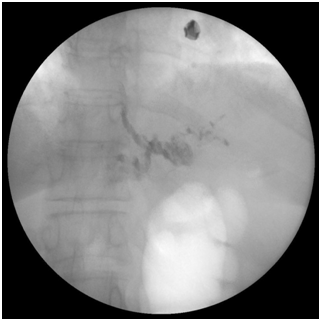

Junctional varices has a significantly high rate of rebleeding as they may be easily missed during endoscopic examination as they are usually multiple and are frequently mistaken for gastric folds especially if they are not actively bleeding. An important observation in our study that we found that varices that occur distal to gastroesophageal junction (classified as GOV1) are not in communication with esophageal varices we reached this conclusion by the observation that in the post injection X ray films, Histoacryl injection of the junctional varices (GOV1) below the Z line showed that the Histoacryl didn’t go up above the Z line, while injection of the esophageal varix above the Z line fills the whole column of the varix (Figure 1).